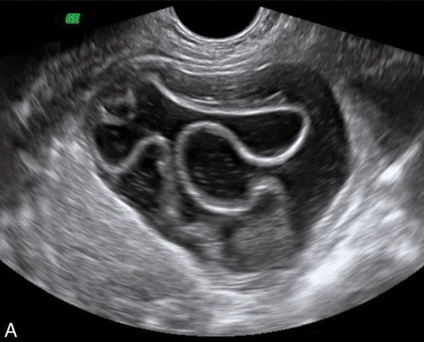

Pelvic kidney